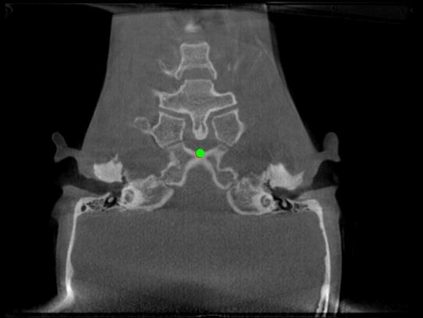

Detecting 3D landmarks on cone-beam computed tomography (CBCT) is crucial to assessing and quantifying the anatomical abnormalities in 3D cephalometric analysis. However, the current methods are time-consuming and suffer from large biases in landmark localization, leading to unreliable diagnosis results. In this work, we propose a novel Structure-Aware Long Short-Term Memory framework (SA-LSTM) for efficient and accurate 3D landmark detection. To reduce the computational burden, SA-LSTM is designed in two stages. It first locates the coarse landmarks via heatmap regression on a down-sampled CBCT volume and then progressively refines landmarks by attentive offset regression using multi-resolution cropped patches. To boost accuracy, SA-LSTM captures global-local dependence among the cropping patches via self-attention. Specifically, a novel graph attention module implicitly encodes the landmark's global structure to rationalize the predicted position. Moreover, a novel attention-gated module recursively filters irrelevant local features and maintains high-confident local predictions for aggregating the final result. Experiments conducted on an in-house dataset and a public dataset show that our method outperforms state-of-the-art methods, achieving 1.64 mm and 2.37 mm average errors, respectively. Furthermore, our method is very efficient, taking only 0.5 seconds for inferring the whole CBCT volume of resolution 768$\times$768$\times$576.